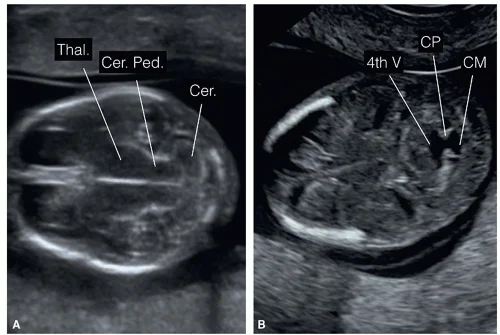

4. Fetal CNS Ultrasound: From Routine Screening to Targeted Neurosonography By Dr. Ekta Mishra

Move beyond routine scans and master targeted fetal CNS imaging.

Session highlights:

• Indications for targeted neurosonography

• Key CNS planes & anatomical structures

• Common abnormalities missed on routine screening

• Clinical and exam-focused imaging pearls

Essential for OBG & Radiology residents, fetal medicine fellows, and exam aspirants.